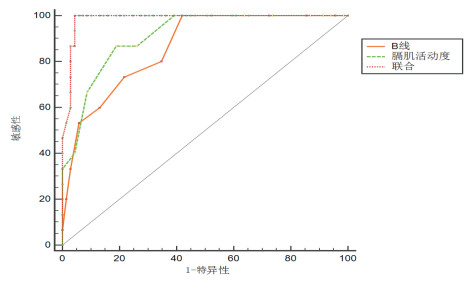

2.3 LUBS与DD、及其联合评价的ROC曲线分析以撤机成功率为因变量,以前文中提及的LUBS、DD及两者的联合评价为变量,通过绘制ROC曲线显示,联合评价的AUC面积为0.985,优于LUBS(AUC=0.862)、DD(AUC=0.91),P=0.019,见图 5,表 3~4。

| 图 5 LUBS、DD、及联合评价的ROC曲线 |

| 指标 | cut-off值 | 约登指数 | 敏感度95%CI | 特异度95%CI | AUC 95%CI | 阳性预测值95%CI | 阴性预测值95%CI | 阳性似然比95%CI | 阴性似然比95%CI |

| LUBS(分) | > 9 | 0.579 | 1.0(0.782~1.0) | 0.579(0.455~0.988) | 0.862(0.77~0.1458) | 0.341(0.205~0.499) | 1.0(0.912~1.0) | 2.38(1.8~3.1) | 0.0 |

| DD(mm) | < 17 | 0.678 | 0.866(0.59~0.98) | 0.811(0.98~0.59) | 0.91(0.82~0.96) | 0.50(0.299~0.70) | 0.966(0.88~0.99) | 4.60(2.7~7.8) | 0.16(0.04~0.6) |

| 联合评价 | > 0.18 | 0.956 | 1.0(0.782~1.0) | 0.956(0.87~0.99) | 0.985(0.93~0.99) | 0.833(0.58~0.96) | 1.0(0.94~1.0) | 47(7.6~98.6) | 0.0 |

| 注:LUBS为肺部超声B线积分,DD为膈肌移动度,联合评价为LUBS与DD联合评价评分,cut-off值为截断值,AUC为受试者工作特征曲线下面积,95%CI为95%可信区间 | |||||||||

| 指标 | AUC | 标准误 | 95%CI | Z值 | P值 |

| LUBS-DD | 0.047 | 0.0678 | -0.085~0.181 | 0.706 | 0.48 |

| LUBS-联合评价 | 0.122 | 0.0454 | 0.0332~0.211 | 2.6145 | 0.007 |

| DD-联合评价 | 0.074 | 0.0318 | 0.0122~0.137 | 2.343 | 0.019 |

ROC曲线的成对对比:①联合评价比LUBS预测撤机成功率敏感度及特异度更高(AUC 0.985比0.862,P < 0.05);②联合评价比DD预测撤机成功率敏感度及特异度更高(AUC 0.985比0.910,P < 0.05);③LUBS对比DD在预测撤机成功率敏感度及特异度差异无统计学意义(AUC 0.862比0.910,P > 0.05)。

根据传统SBT预测撤机成功率约为74.92%[12],单独应用肺部超声LUBS、膈肌移动度的指标对预测撤机成功与否亦有一定价值,但单一指标的敏感度、特异度、阳性预测值均不高;在某些特殊患者的撤机过程中存在一定局限性。比如膈肌麻痹患者,当肺部炎症控制、心功能改善的情况下,由于膈肌活动障碍,无法提供足够的潮气量,因此单一的LUBS评估并不能可靠的预测撤机的成功率。本研究将LUBS与DD同时纳入撤机前的评估,个体化的反应了患者的心肺功能、膈肌功能的状态。对145例机械通气24 h以上的危重患者进行研究,通过绘制ROC曲线显示,联合评价的AUC面积为0.985,优于LUBS(AUC=0.862)、DD(AUC=0.91),P=0.019;LUBS的截断值为<9分,DD的截断值为>17 mm,撤机成功敏感度100%,特异度95.6%,阳性预测值为0.833,阴性预测值为1.0,提示联合评价对预测撤机过程成功率具有更高的准确性。

值得一提的是, 本文中用于预测拔管成功时,想问的是“我的指标(LUBS、DD或联合评价)阳性了,患者会不会拔管失败呢?”,更进一步推广到临床语言则是“我拿到一个指标是阳性时,我有多大把握判断对象真的有病”?而回答这个问题的答案就是阳性预测值,同理也适用于阴性预测值。本研究发现三者的阳性预测值分别为0.341,0.50和0.833,阴性预测值分别为1.0、0.966和1.0,也就意味着这三者阴性时,都有大于95%的把握认为拔管不会失败,而阳性时,仅依靠LUBS或DD,笔者认定患者拔管将会失败的把握还不到一半,而通过二者的联合,把握性提高到了83.3%,这正是本研究提出联合应用二者的意义所在。当然,必须说明的是,预测值的高低与疾病的发病率密切相关,这是预测值的局限性所在。